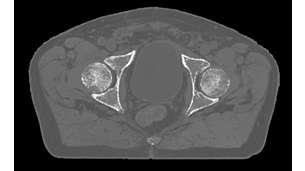

MR-only radiotherapy planning

MRCAT lets you plan radiation therapy based on one MR exam. By excluding the need for CT, this helps relieve the burden on your clinical resources, reimbursement obligations and budget. And your patient is spared to undergo a second scan – reducing the patient burden.